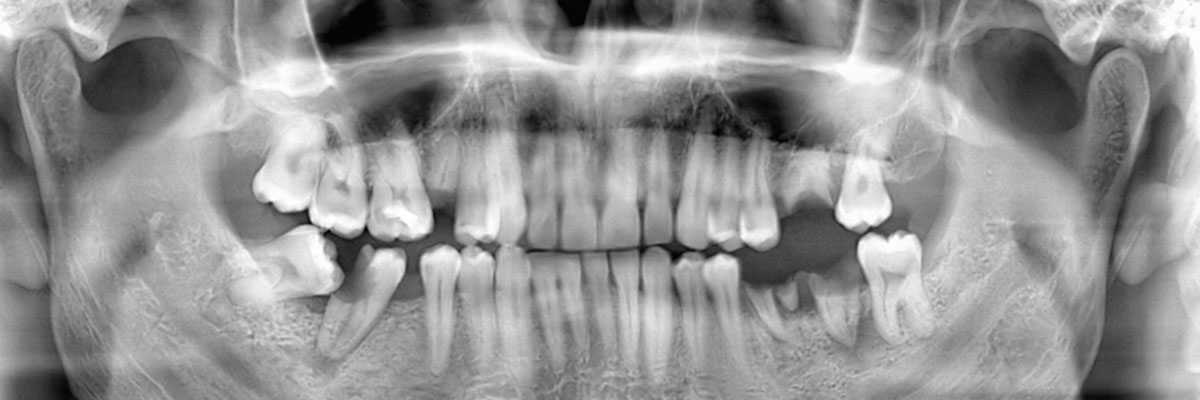

You may need a wisdom teeth extraction at some point in your life. It is rare for a person to have enough room for all of their wisdom teeth, and as a result, they tend to grow in impacted. This can be uncomfortable, pushing your other teeth forward and creating a space for food to become trapped; it can also increase your risk of infection and decay. This is why we often recommend that our patients have their wisdom teeth removed. When you schedule an appointment with Impladent Implant & Cosmetic Dentistry, we can examine you, take X-rays, and let you know if and when you should schedule an extraction procedure. You can reach us by calling (714) 677-9452.

At Impladent Implant & Cosmetic Dentistry, we understand that each of our patients is unique and so are their teeth. Whether or not you need to have your wisdom teeth removed by a dentist, will really depend on the size of your palate. If you have plenty of room for all of your teeth and your third molars, they can stay in place. There is no point in removing something that grows in straight and is healthy. However, any tooth that grows in impacted needs to be removed because it is posing a direct threat to your other teeth and roots in addition to being a target for infections. The best way to find out if your wisdom teeth should be removed is to call 714-677-9452 and schedule an appointment with our Anaheim dentist office. We can make a recommendation and answer any other questions you have about the procedure itself.